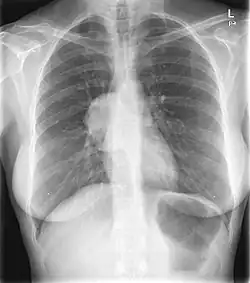

Hilum overlay sign

This PA chest radiograph demonstrates an abnormal contour in the right hilar region, with visualization of the pulmonary vessels through the mass (the hilar overlay sign) indicating its posterior mediastinal location. On resection this was found to be a benign solitary fibrous tumor of the pleura.

The hilum overlay sign is an imaging appearance on chest radiographs in which the outline of the hilum can be seen at the level of a mass or collection in the mid chest.[1] It implies that the mass is not in the middle mediastinum, and is either from anterior or posterior mediastinum(most of the masses arise from the anterior mediastinum).[2]